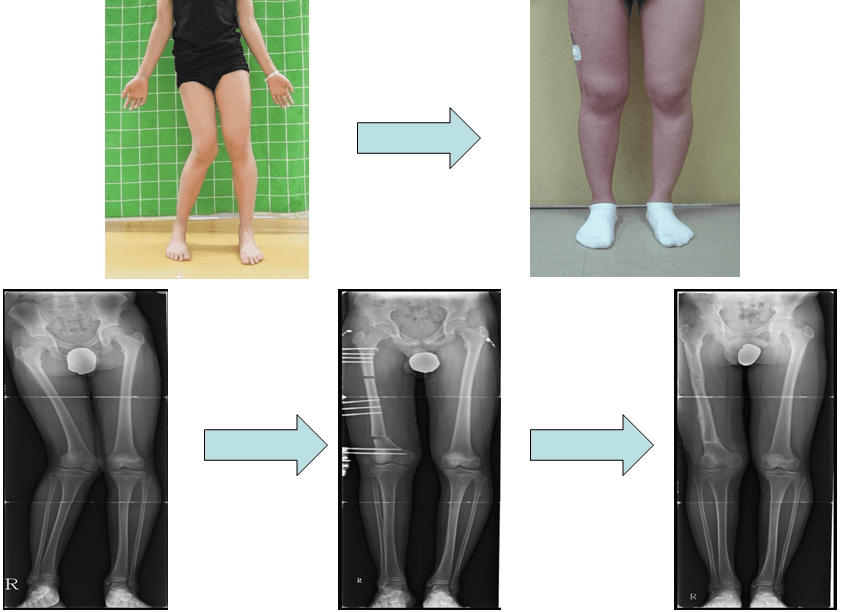

After a knee joint injury, one leg was bowed outwards, and I received a femur correction and now have straight legs.

Perform correction surgery on femur to correct the valgus deformity of a leg, resulting straightened legs.